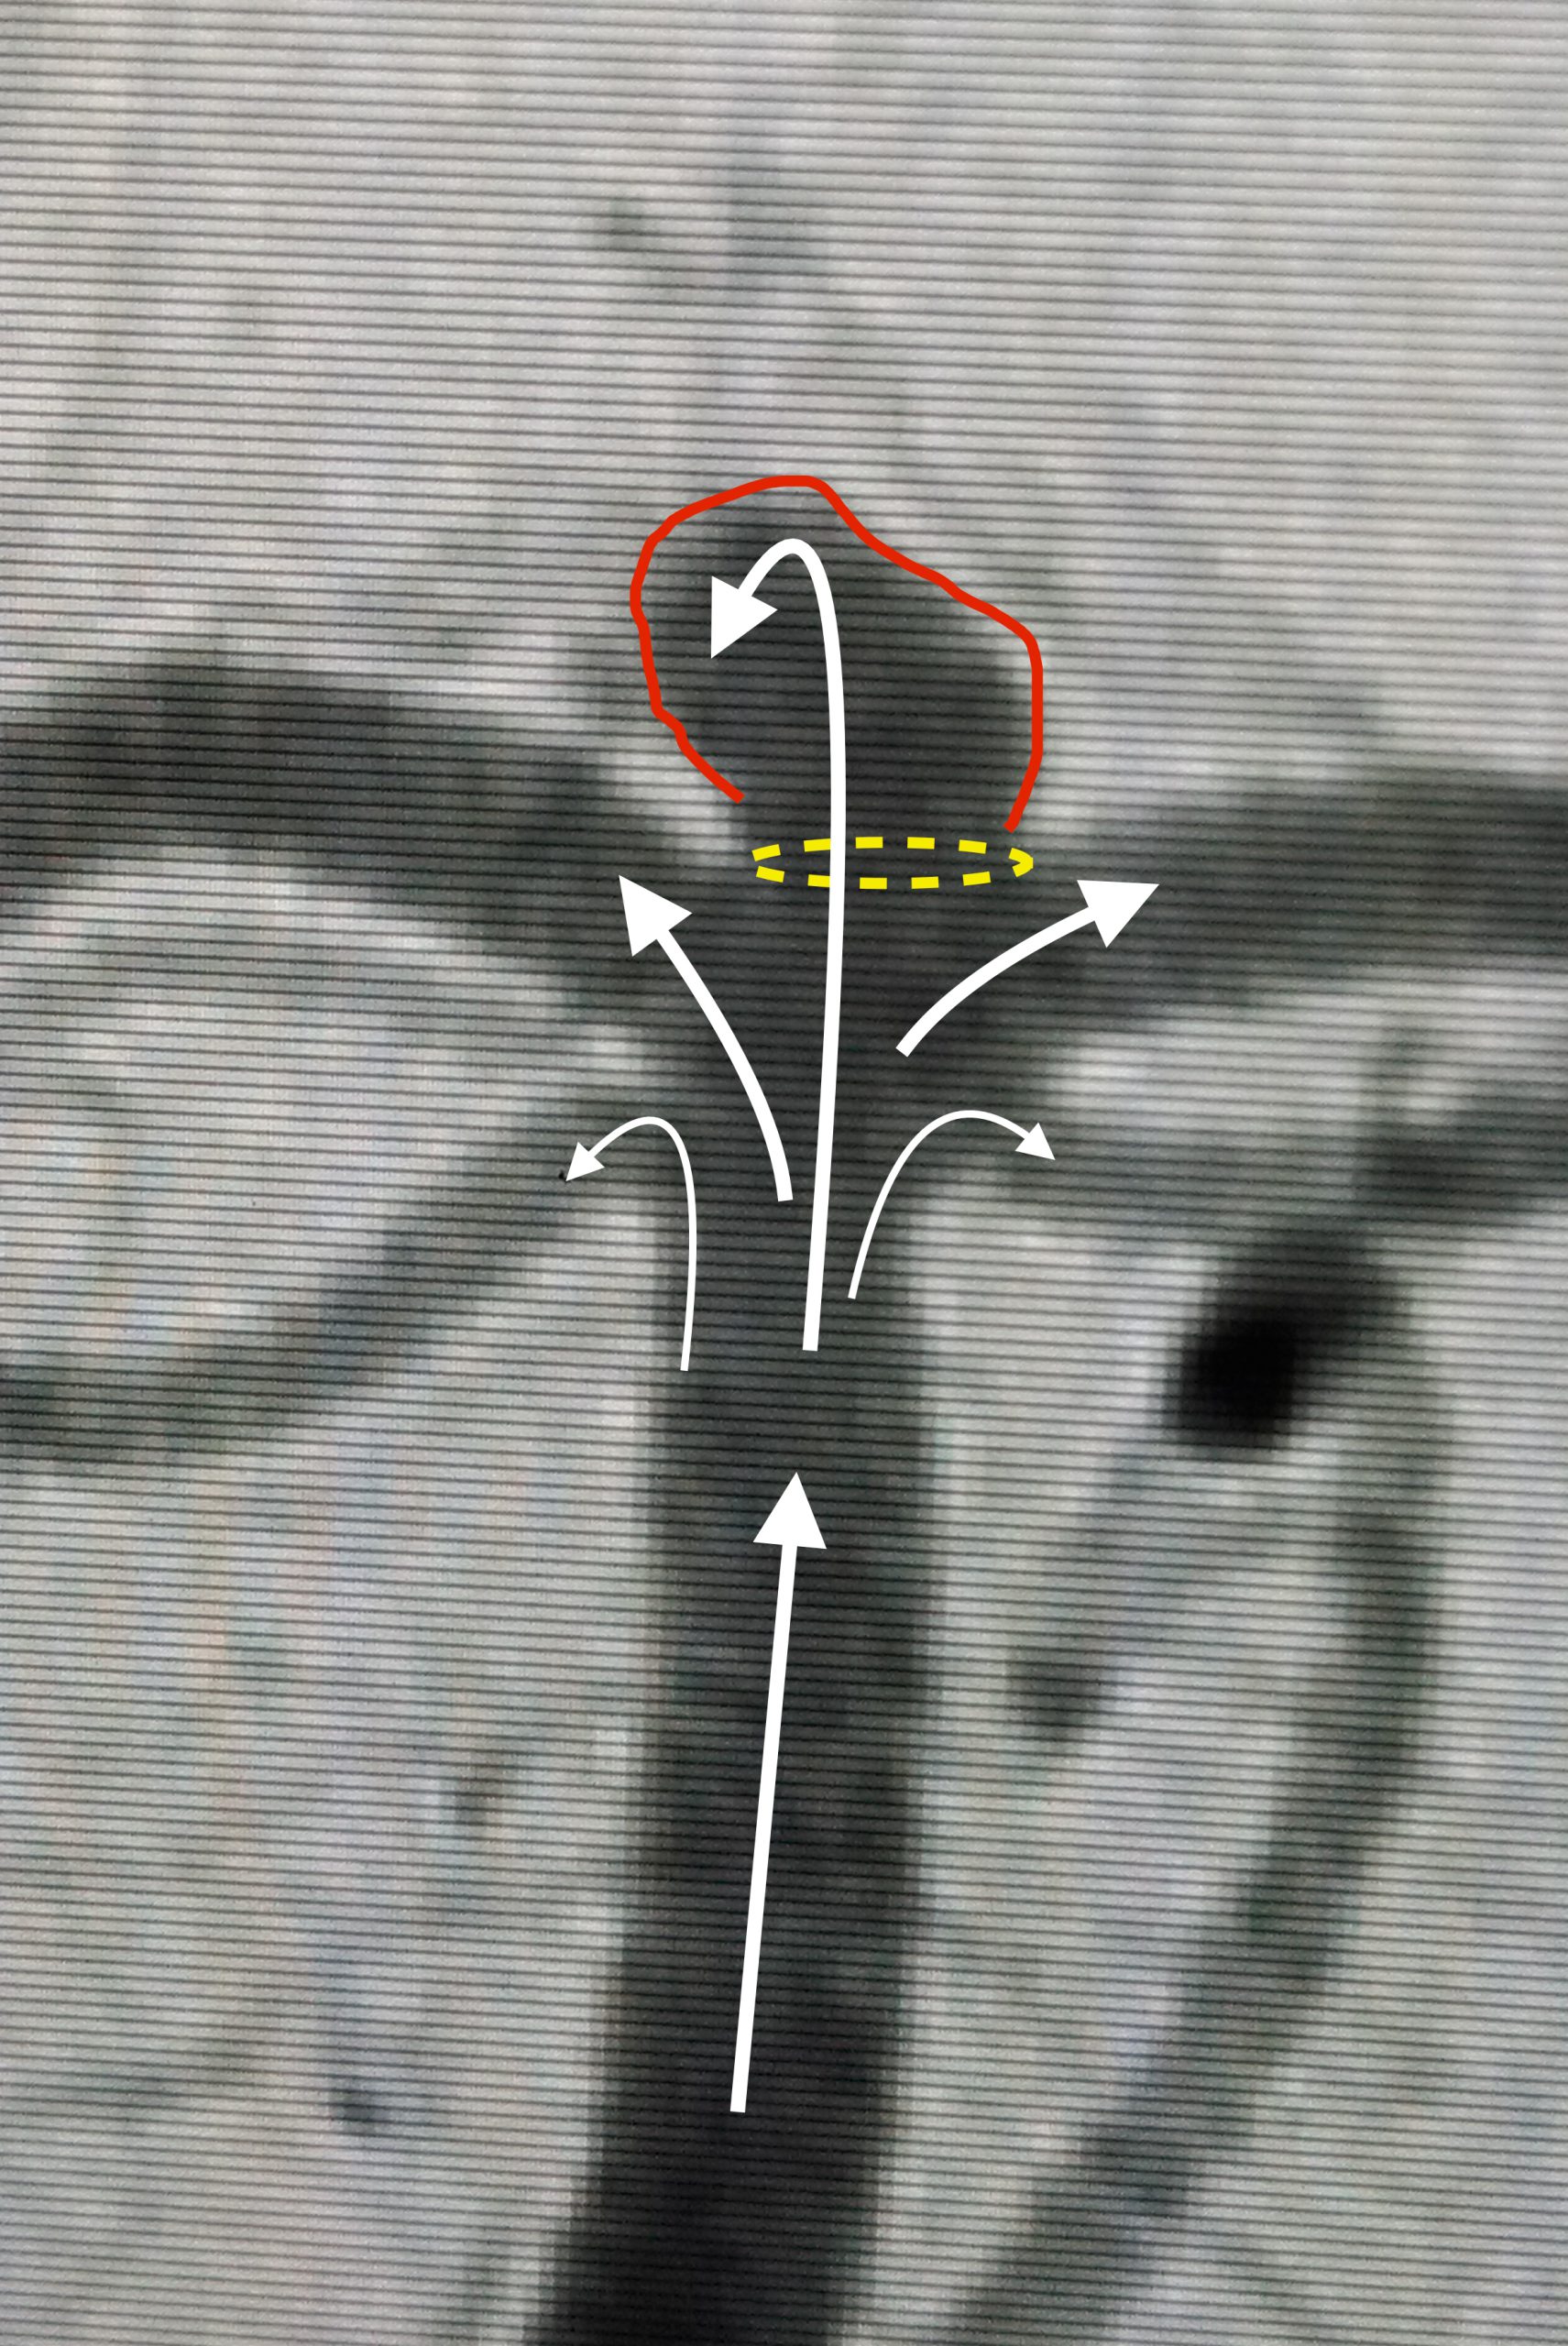

Spinal decompression therapy is a gentle, non-invasive treatment that gradually stretches the spine in a controlled manner. This process reduces pressure on the spinal discs and nerves, which can help relieve pain and improve spinal function.

The therapy involves a series of sessions where a specialized traction table or device gently stretches and relaxes the spine. This movement creates negative pressure within the discs, allowing bulging or herniated discs to retract and take pressure off surrounding nerves. It also improves blood flow, bringing nutrients and oxygen to the area to promote healing.